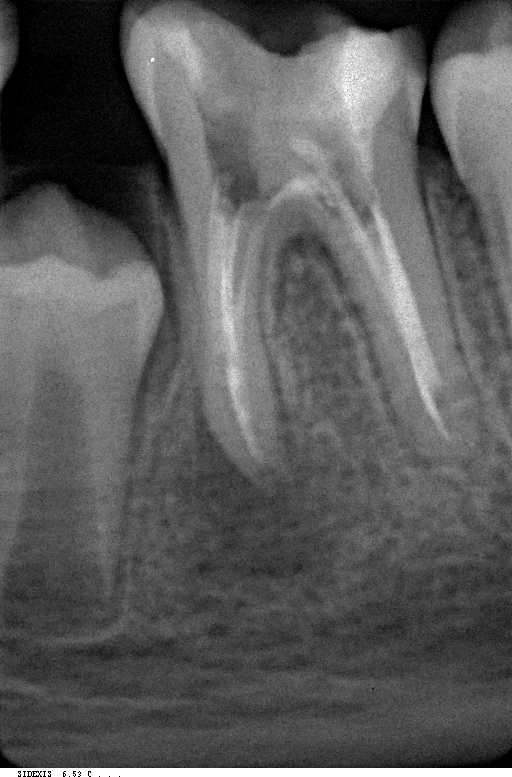

Эндодонтия

Эндодонтическое лечение зубов под микроскопом